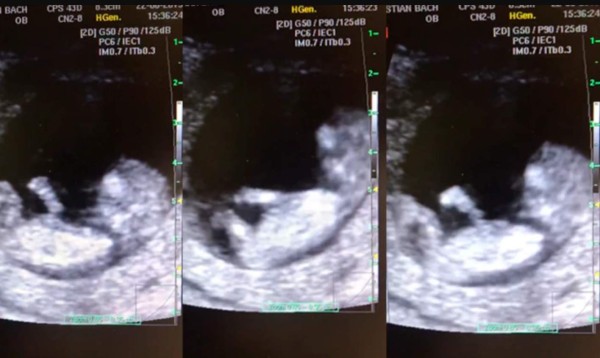

El video viral compartido en el Facebook del doctor muestra un increíble ultrasonido de una de sus pacientes, en el que claramente se ve cómo el bebé de 12 semanas de gestación, realiza resbaladillas en el vientre de su madre, como si se tratara de un parque de diversiones.

El doctor se maravilló con tal acción y pidió permiso a su paciente Itzel para compartir el material. El doctor asegura que es completamente normal que un bebé con 12 semanas pueda realizar tal acción, pero asegura que lo que lo sorprendió es que los movimientos del bebé fueran tan coordinados y repetitivos.